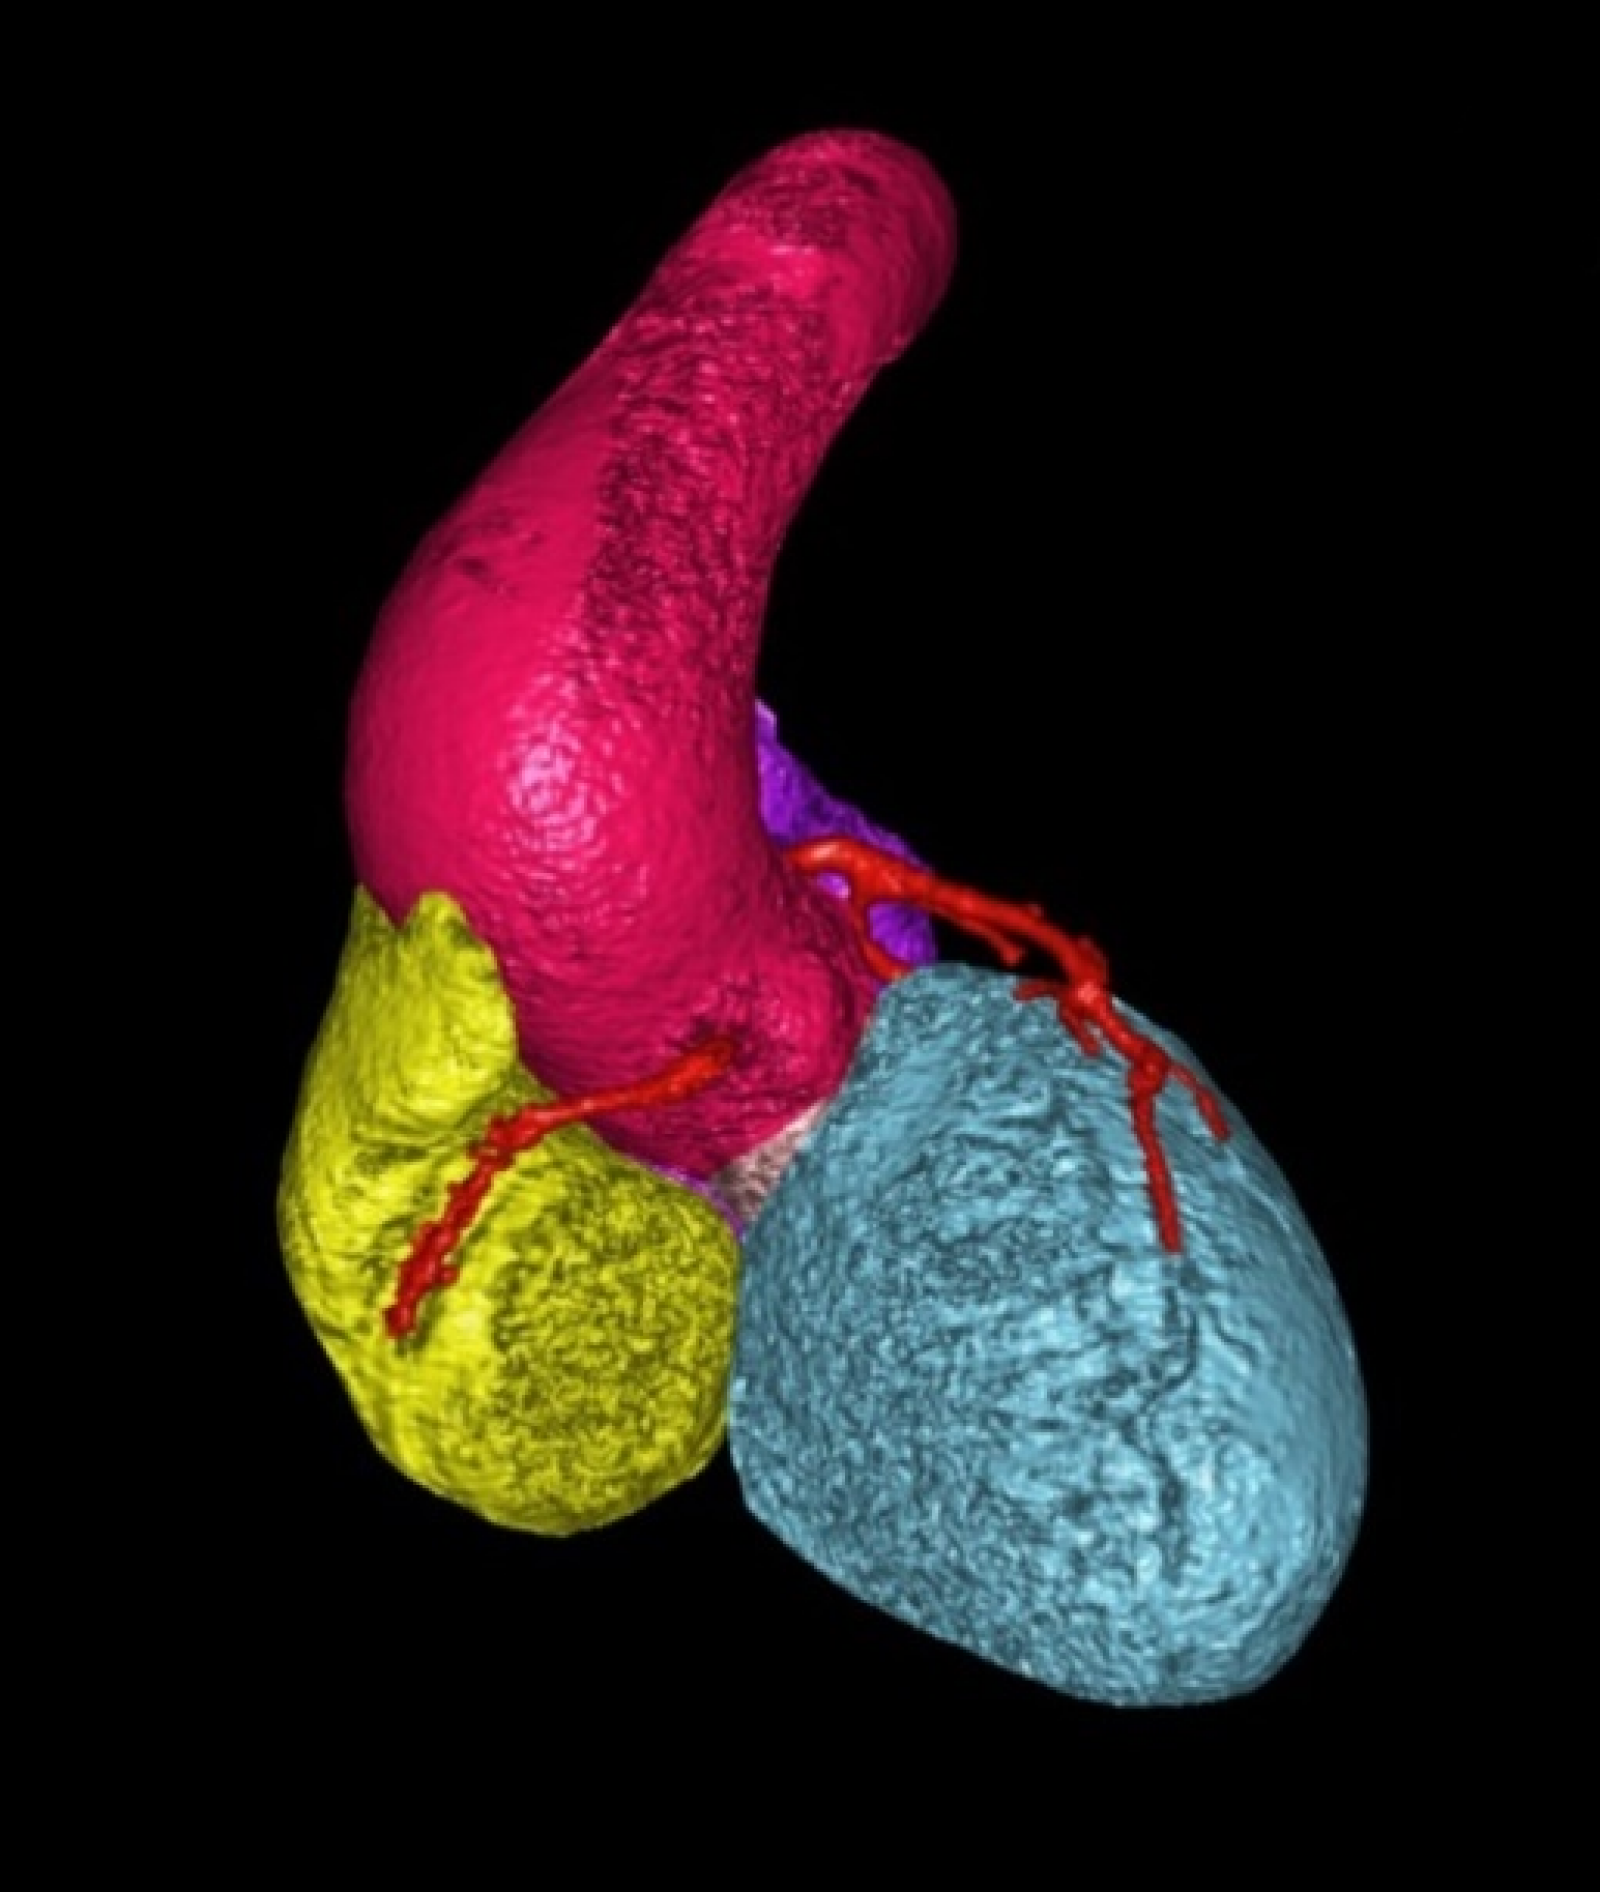

Centrum komplexní péče o vrozené srdeční vady v dospělosti vzniklo  v roce 2015  díky spolupráci  Centra kardiovaskulární a transplantační chirurgie s Interní kardiologickou klinikou Fakultní nemocnice  Brno a nabízí zcela komplexní péči o dospělé nemocné s vrozenou srdeční vadou. Portfolia jednotlivých pracovišť se navzájem doplňují.  Centrum poskytuje ambulantní sledování pacientů se všemi typy vrozených srdečních vad, neinvazivní a invazivní diagnostiku včetně transesofageální echokardiografie s využitím 3D zobrazení.  Centrum kardiovaskulární a transplantační chirurgie Brno provádí operace, reoperace a  intervenční výkony u vrozených srdečních vad a současně se věnuje chirurgické léčbě pokročilého srdečního selhání vč. implantace mechanických srdečních podpor a transplantace srdce ( Tým lékařů , seznam prováděných operačních a intervenčních výkonů).  V rámci Interní kardiologické kliniky FN Brno poskytuje invazivní  řešení arytmií ( radiofrekvenční ablace, kardiostimulace vč. resynchronizační léčby), některé intervence (uzávěry defektů septa síní) , organizaci nekardiálních operací a péči o gravidní včetně porodu probíhají v rámci Interní kardiologické kliniky FN Brno.   Návaznost na kardiologii dětského věku je zajištěna spoluprací s Fakultní dětskou nemocnicí v Brně.  Ambulantní péče probíhá na obou klinikách paralelně.